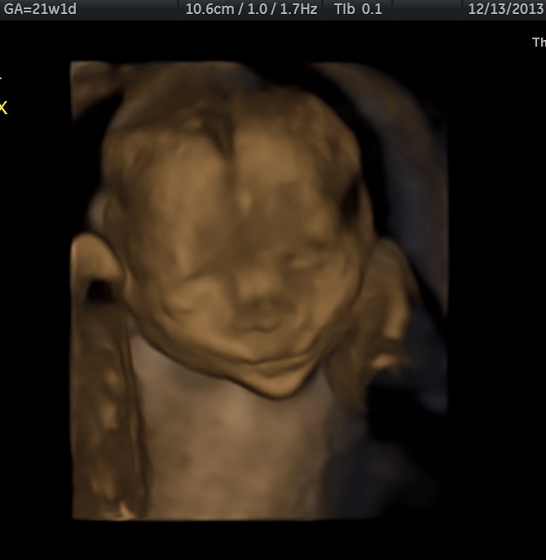

Updates? just got confirmation on Friday it's definitely two boys!! Anatomy Scan went great, they look perfect and are estimating 8 oz each!